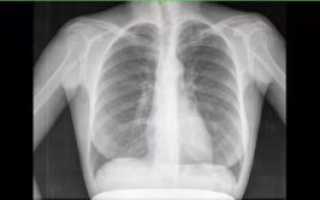

Рассмотрим для примера рентгеновский снимок легких в норме:

На нем визуализируется множество затемнений и просветлений (белого и черного цвета), которые могут запугать читателей. На самом деле эта рентгенограмма расшифровывается просто (см. следующий снимок)

На рентгенограмме подписаны все анатомические структуры, чтобы читателям было легко разобраться. Предлагаем запомнить интенсивность легочных полей. Норма не предполагает наличия патологических затемнений (белого цвета) и просветлений (темного цвета), которых нет на изображении.

Если «набить глаз», научитесь четко отличать норму от патологии.

Рентген здоровых легких описывать следует по классическому стандарту. Вначале вносятся записи о патологических рентгеновских синдромах, затем легочные поля, корни, купола диафрагмы, реберно-диафрагмальные синусы, сердечная тень и мягкие ткани.

Классический алгоритм описания здоровых легких:

- В легочных полях без видимых очаговых и инфильтративных теней;

- Корни не расширены, структурны;

- Контуры диафрагмы и реберно-диафрагмальные синусы без особенностей;

- Сердечная тень обычной конфигурации;

- Мягкие ткани без особенностей.

Вышеприведенная рентгенограмма подпадает под данное описание.